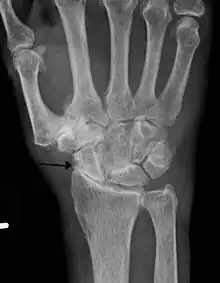

Diagnosis is made with reasonable certainty based on history and clinical examination.[52][53] X-rays may confirm the diagnosis. The typical changes seen on X-ray include: joint space narrowing, subchondral sclerosis (increased bone formation around the joint), subchondral cyst formation, and osteophytes.[54] Plain films may not correlate with the findings on physical examination or with the degree of pain.[55]

Severe osteoarthritis and osteopenia of the carpal joint and 1st carpometacarpal joint